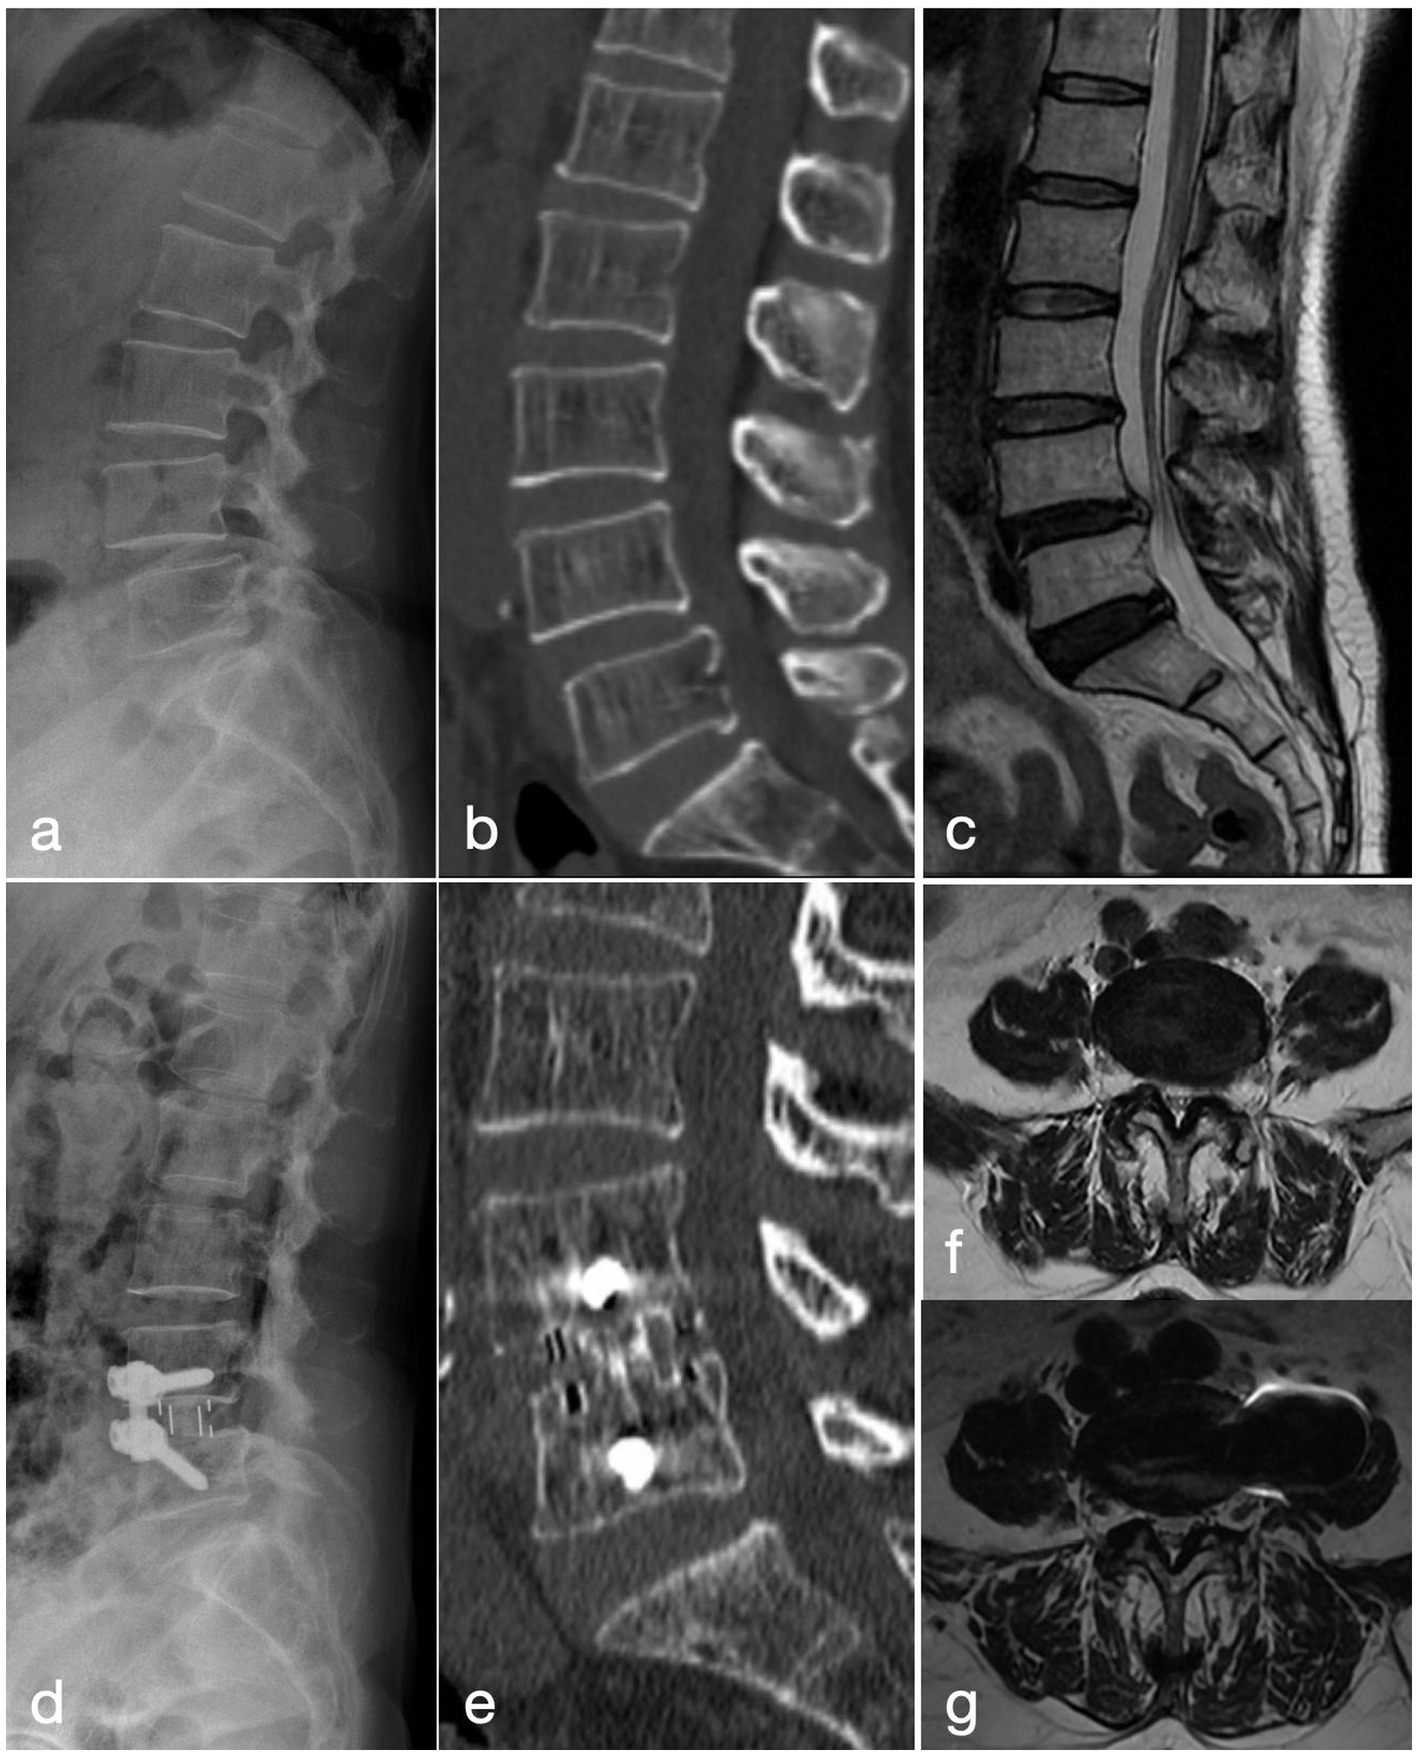

Figure 2

A 57-year-old woman with recurrent low back pain and lower limb intermittent claudication of 9 months’ duration, was treated with the MIS-TLIF procedure. (a–c) Pre-operative lateral radiograph, CT and MRI show grade-I anterior spondylolisthesis of L4. (d) Post-operative lateral radiograph demonstrates well-positioned instrumentation and interbody cage with good reduction of the slip. (e) CT at 2 years confirms solid interbody fusion at L4/5. (f) Pre-operative MRI reveals severe L4/5 central canal stenosis. (g) MRI at 2 years shows increased canal volume and patent cerebrospinal fluid signal.